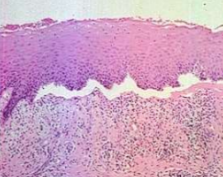

Histopathology:

Mucous membrane pemphigoid showing characteristic subepithelial separation (antibodies directed against basement membrane proteins)

PEMPHIGOID Biopsy Results

Subepithelial separation

Deposition of IgG and C3 at the basement membrane zone